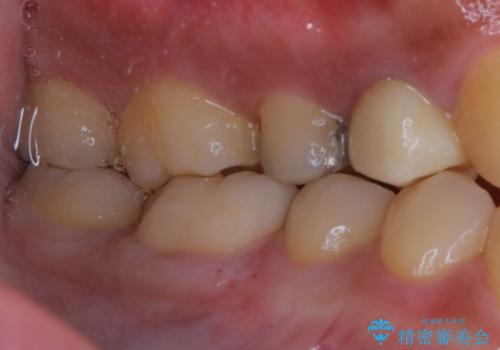

- セラミックへのやり替えを希望された患者様です。

日常的に食いしばる癖があり、歯の表面にはエナメルクラック(歯の表面にできる細かい破折線)も複数認められたため、セラミッククラウンによる治療をご提案しました。

歯ぎしりや食いしばりの癖がある方にはナイトガードの使用も併せてお勧めしています。

適合不良の補綴物は二次的な虫歯発生のリスクが高まります。

自費診療で用いられる材料は保険適応の材料に比べて、より精密で適合の良い被せ物作ることができるため、長期的な虫歯のリスクを大幅に減らすことが可能です。